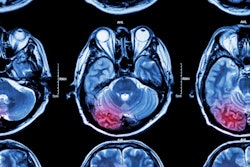

If they're not careful, radiologists can miss significant unexpected findings in emergency department (ED) patients, according to a presentation on May 5 at the annual meeting of the American Roentgen Ray Society (ARRS) in New Orleans.

Potential missed findings include cancer, infection, pseudoaneurysm, fracture, and bowel perforation, according to an electronic exhibit at the meeting. First author Dr. Willie McClure of the David Grant USAF Medical Center at Travis Air Force Base in California and colleagues shared five cases that had obvious findings when recognized but which were not reported due to "tunnel vision" by the interpreting radiologists.

The authors presented five cases at ARRS 2022, including a round white ball in the spleen that should be considered to represent a pseudoaneurysm until proven otherwise. The cases also encompassed a variety of imaging modalities, including x-ray, fluoroscopy, CT, ultrasound, and MRI.